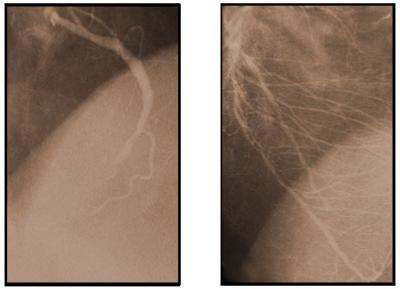

The new research findings demonstrate that cardiac ischemia plays an important role in adenovector gene transfection (delivery) in mammalian hearts. Based on this understanding, using a standard balloon angioplasty catheter, researchers have developed and tested a new method to induce transient ischemia during a non-surgical interventional cardiac procedure, which when coupled with the infusion of nitroglycerin, boosts the delivery (cell transfection) of an adenovector gene construct into heart cells. The increase in adenovector-based gene transfection with the new technique is over two orders of magnitude (>100 fold).

Cardium's new method of adenovector delivery takes advantage of the findings that transient ischemia appears to alter the permeability barrier of the vascular endothelium and may expose the blood to the coxsackie-adenovirus receptor mediating adenovector uptake by the heart. Balloon angioplasty catheters have been used for many years to dilate blocked coronary arteries, sometimes with use of a stent, and these catheters have also been used safely by cardiologists in patients with coronary artery disease to study the effects of brief ischemia. Cardium's new technique inflates the balloon in non-narrowed areas, and only enough to briefly interrupt flow using inflation pressure that is less than that used for performing angioplasty.

Cardium's recently initiated Russian-based ASPIRE Phase 3 / registration clinical study uses transient ischemia techniques during non-surgical percutaneous catheterization with a standard angioplasty catheter together with the intracoronary infusion of nitroglycerin with the Generx® [Ad5FGF-4] product candidate for the treatment of patients with myocardial ischemia and stable angina pectoris. These patients have atherosclerotic coronary artery disease, and the Company's Generx product candidate is intended to stimulate the growth of new or additional collateral blood vessels to bypass blockages.